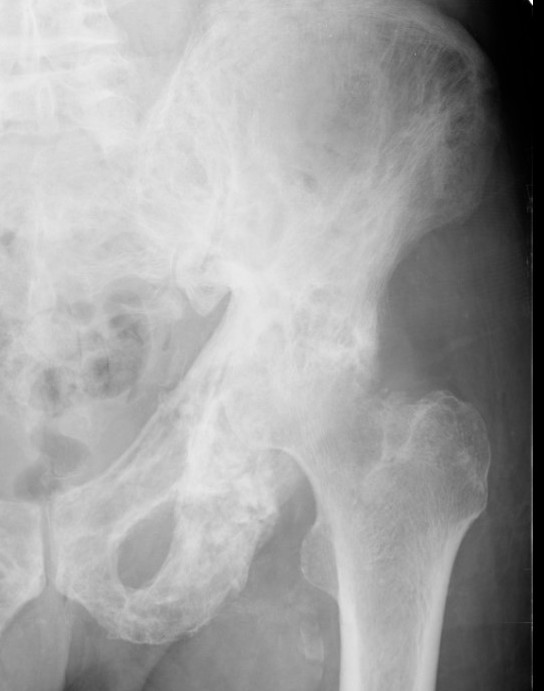

Pelvis

Coxa vara / protrusio / OA

Hip osteoarthritis with coxa vara and protrusio

THA

Technical issues

Acetabulum

- difficult reaming due to hard bone

- protrusio - consider medial bone graft / cages / lateral offset liners

- limited ability for cement interdigitation - uncemented cups may be preferrred

Femur

- coxa vara - risk varus femoral implants

- difficulty broaching femur - may need burrs

- femoral bowing - may need osteotomy

- poor cement interdigitation - uncemented stems may be preferred

- brittle bone - increased risk fracture

Heterotopic ossification

- high risk

Progression of disease and loosening of cemented acetabular component